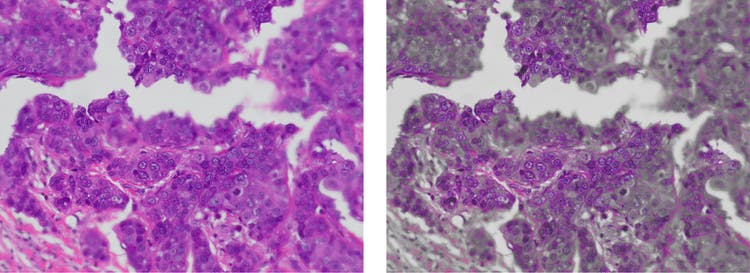

OSIA (Olympus Smart Image Averaging): Riduce il rumore e elimina artefatti, mantenendo una veloce frequenza di quadro

Riduzione del rumore mediante la media delle immagini in fotocamere per microscopi digitali

Confronto tra immagine senza applicazione dell'OSIA (a sinistra) e immagine con applicazione dell'OSIA (a destra)